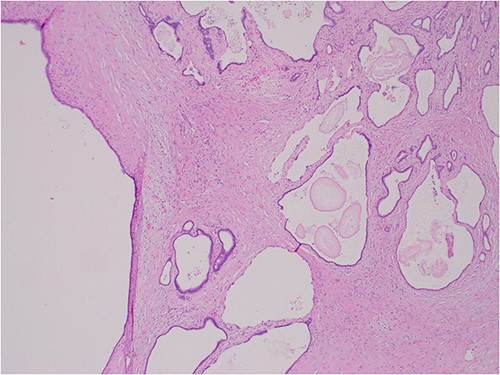

The histologic examination revealed numerous large, medium and small cysts separated by prominent stromal areas of fibrosis. These areas contained luminal eosinophilic concretions (Fig. 3). No ovarian-type parenchyma was found to suggest IPMN. The cyst formation maintained the outline of the native lobules, with some withered central islets appreciated. No papillary architecture was observed, and no epithelial dysplasia or invasive carcinoma was present. Epithelium lining the cysts was attenuated in some areas, and cuboidal in others. Where the epithelium was recognizably cuboidal, there was scattered acinar differentiation noted, characterized by apical cytoplasmic granules positive on periodic acid-Schiff-diastase (PASD) staining (Fig. 4). Acinar differentiation did not therefore have to be confirmed with further immunohistochemistry.

PASD × 200 showing positive apical staining in cyst-lining epithelial cells, indicating acinar differentiation.